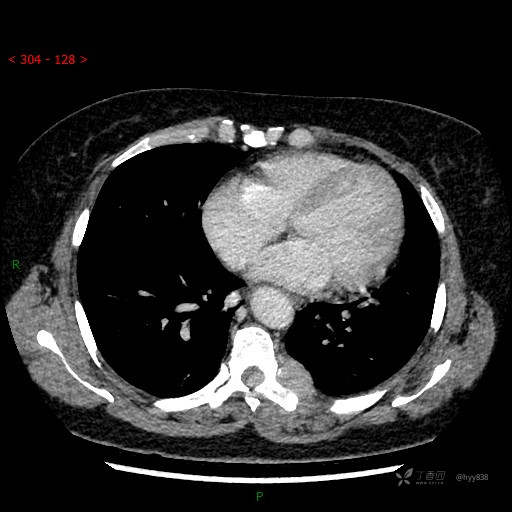

增强